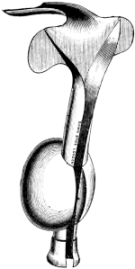

| 209. | Eustachian Catheter | 365 |

| 210. | Passing the Eustachian Catheter | 365 |

| 211. | Passing the Eustachian Catheter | 365 |

| 212. | Passing the Eustachian Catheter | 366 |

| 213. | Passing the Eustachian Catheter | 366 |